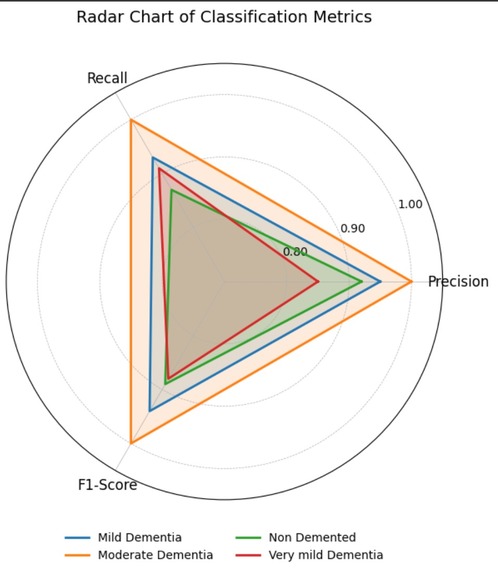

Radar chart for Metrics across different Alzheimer classes